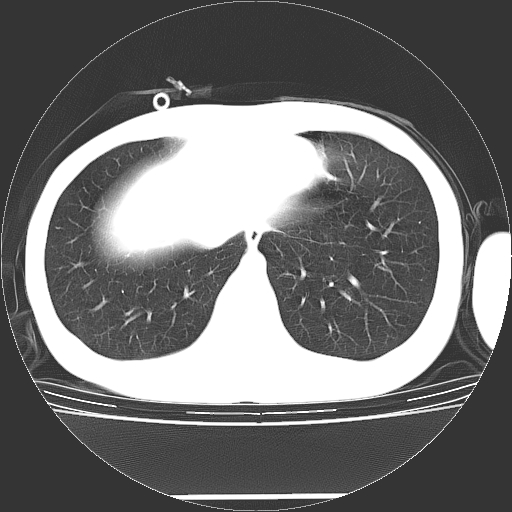

标题: CT19767:男,20岁,右侧气胸行闭式引流术后五天CT检查。 [打印本页]

男,20岁,右侧气胸行闭式引流术后五天ct检查看肺内是否有肺大泡,纵隔窗未见异常,未上传。

1)右侧胸腔闭式引流术后导管留置。2)右肺未见肺大泡。

未见肺大泡,还有微量气体。